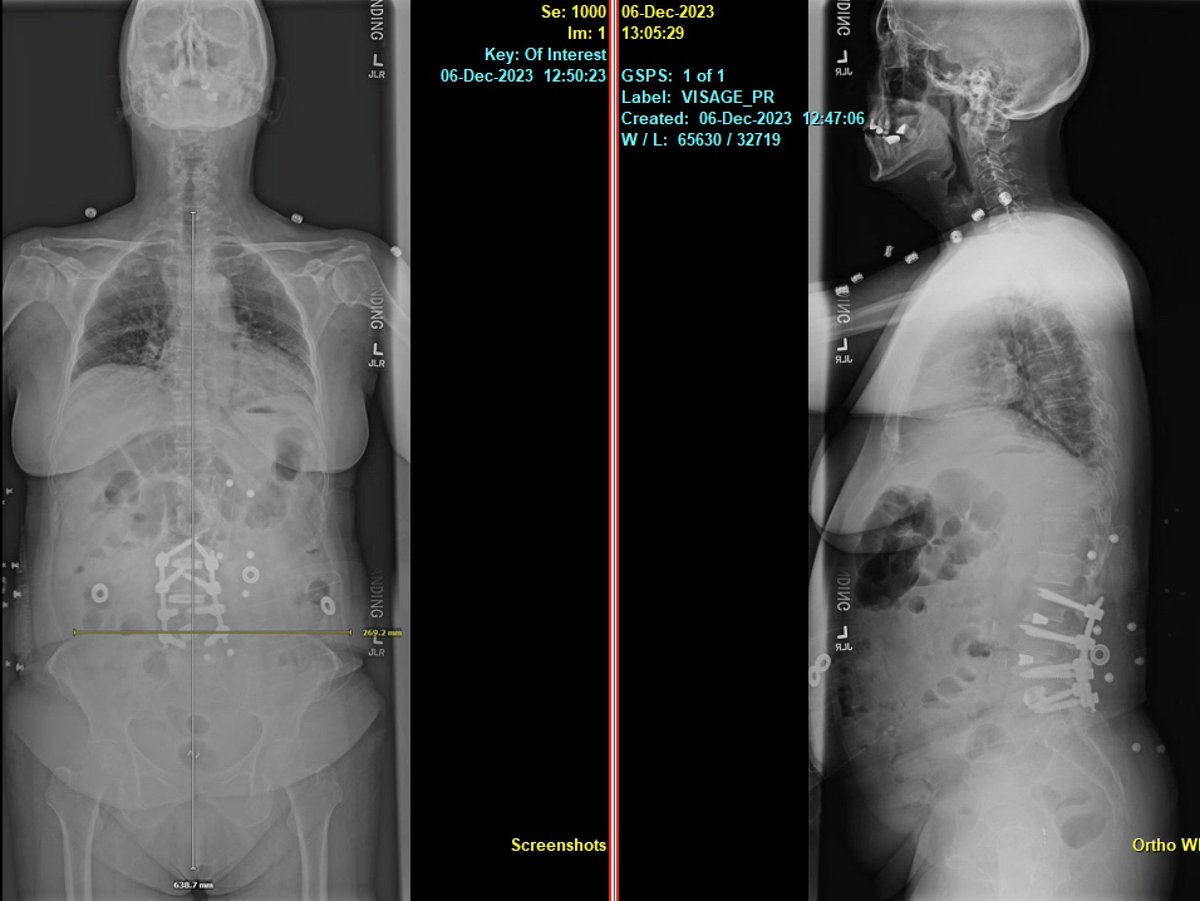

Awake MIS fusion to correct this patient scoliosis. @mayoclinic fellowship @RodNavarroM teaches endoscopic, lateral, MIS awake and deformity. Learn enabling technology & freehand. Accepting fellowship application for 2024-2025. @DoctorQMd @wchrisfox @oakinduroMD @StephenPirrisMD

Pre-and post-op awake MIS fusion to correct this patient scoliosis. @mayoclinic our associate surgeon @RodNavarroMD work hand in hand to learn the latest approach, enabling technology and freehand. Accepting applications for 2024-2025. @DoctorQMd @oakinduroMD @wchrisfox